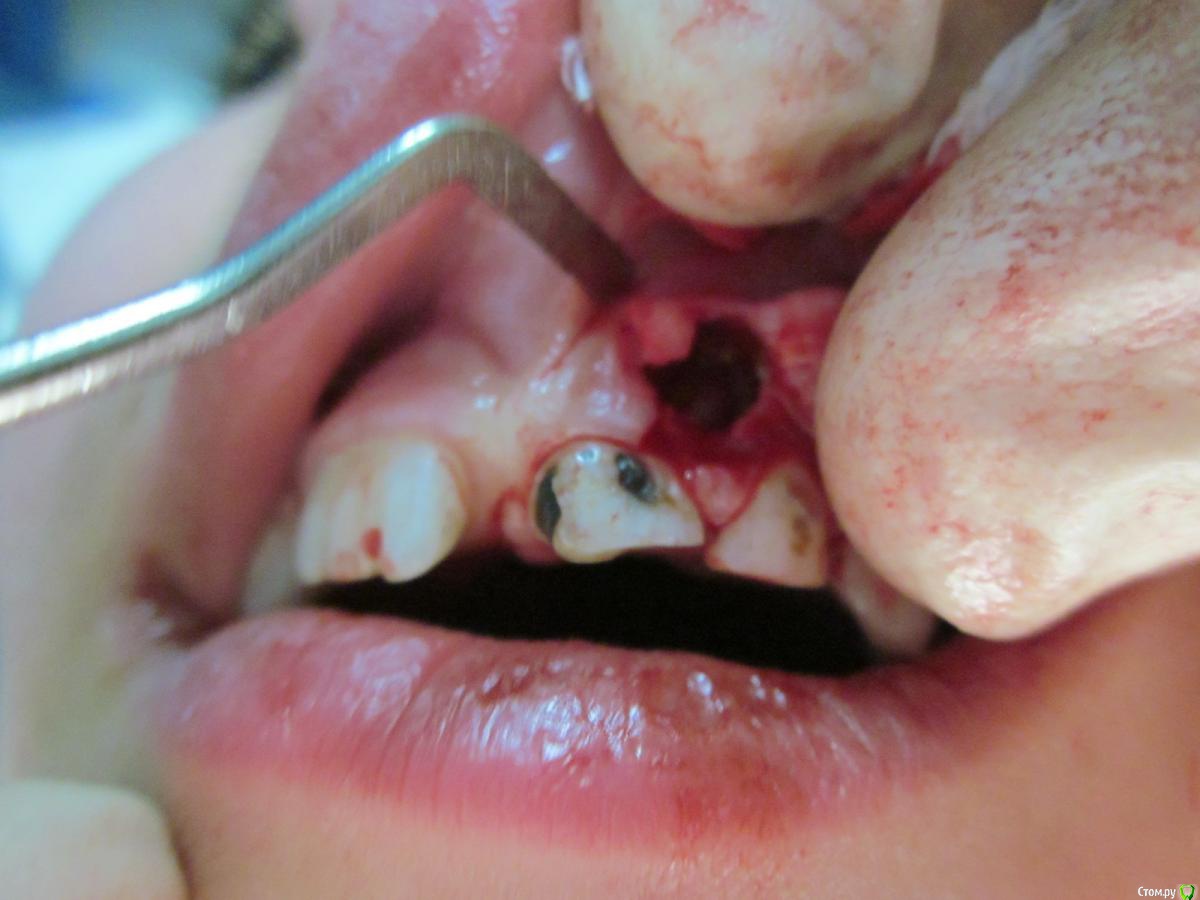

По данному случаю: пациент 6-7 лет, 21 не растёт, все динамят (ортодонты и терапевты), дошли до хирурга: на снимок прицельный, что то не то, на КТ охарактеризовал как одонтому. Операция под

анестезией Ультракаин дс, кортикальную пластинку трепанировал «расковырял» эскаватором, убрал конгломерат тведых тканей, саму оболочку, удалил 61. Биологический материал в пробирку с физ

раствором, направление на исследование в гистологию и ГОУ самим.

На перевязках ничего особенного, швы убрал на 7–е сутки, результаты анализов не принесли, и потом пропали. Прорезался 21 или не не знаю, вызвонивать не стал.